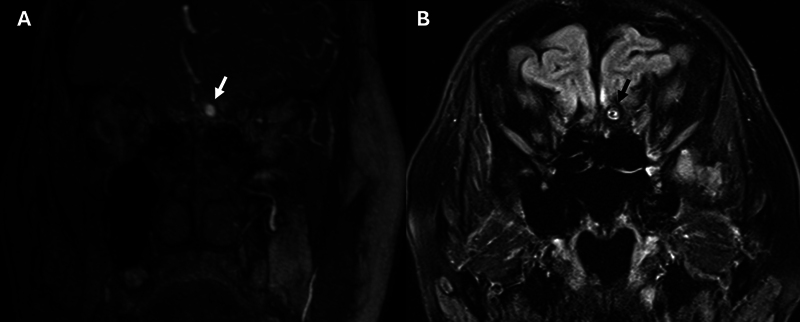

Spontaneous acute subdural hematoma is uncommon and usually caused by coagulopathy or other bleeding disorders, malignancy, intracranial hypotension, and abnormal intracranial vessels. We present unique cases of acute spontaneous subdural hematoma from moyamoya disease. There are a few cases reported, and we review previous literature and describe bleeding sources from aneurysms related to moyamoya disease in highly unusual locations.